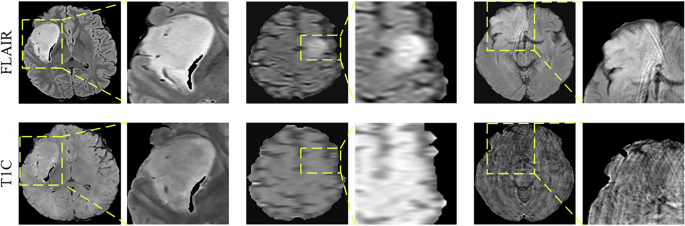

Although SSL-MISS-Net demonstrates overall superior performance compared with current state-of-the-art methods, prediction errors still occur in cases with low image quality or complex tumor characteristics, as illustrated in the Fig. 13. Such cases typically suffer from motion artifacts, low signal-to-noise ratios, or image corruption, which result in blurred images or reduced contrast between the tumor and surrounding tissue, making it difficult for the model to capture critical discriminative features. Moreover, the current gold standard for molecular features and pathology types is established through histological and molecular analyses of biopsy sample from the tumor region. However, given the intratumoral heterogeneity, biopsy samples may not fully represent the molecular characteristics of the entire tumor. As a result, in certain cases, the gold standard itself may contain a degree of uncertainty, which could influence the evaluation of the model.

Some sample images with incorrect predictions.